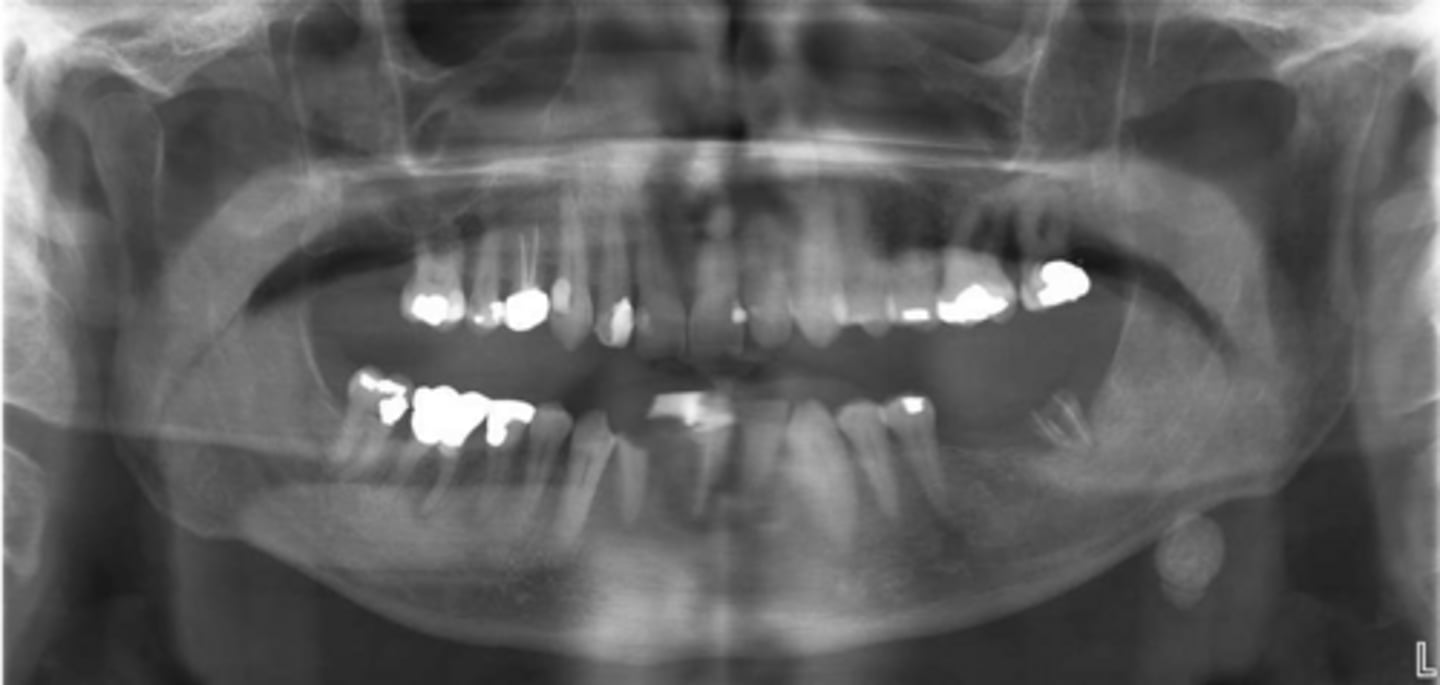

ID the pathology:

Swelling in wharton's duct

Sialolithiasis

ID the pathology during surgery:

Associated with pain upon salivation

What pathology is associated with pain upon salivation?

submandibular gland

80% of Sialolithiasis are associated with what gland?

Radiopaque mass

What is the radiographic features of a

Sialolithiasis?

ID the pathology based on the histology findings:

- Laminated calcified structure with central nidus

- Milking stone toward duct orifice